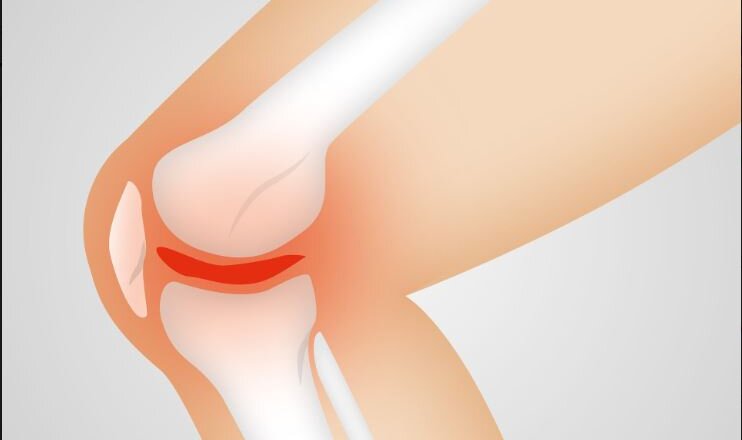

Τι συμβαίνει όταν μια επιγονατίδα εξαρθρωθεί

Ο καλύτερος τρόπος για να μειώσετε την πιθανότητα οξέων και χρόνιων εξαρθρώσεων της επιγονατίδας είναι να διατηρήσετε τη συνολική δύναμη του ποδιού, του τετρακέφαλου και του ισχίου.